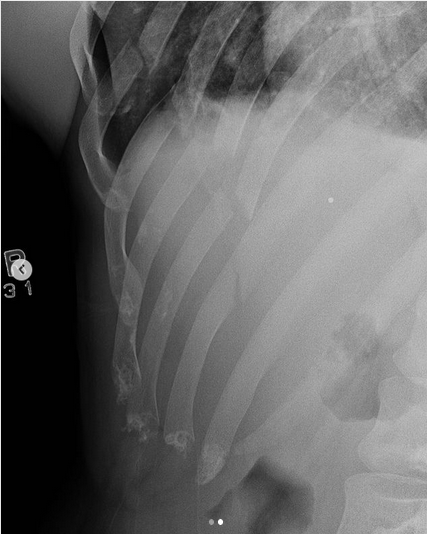

Sportivul a ajuns la spital cu cinci coaste rupte și un plămân perforat.

Chance Rencountre a terminat la podea lupta cu Andrey Koreshkov, după ce acesta i-a aplicat o lovitură de picior care l-a trimis direct pe masa de operație. Sportivul a fost diagnosticat cu cinci coaste rupte și un plămân perforat, dar medicii și-au făcut datoria și acum el este în afara oricărui pericol.

Sportivul a ținut să își liniștească personal fanii prin intermediul unui mesaj postat pe rețelele de socializare. Acesta a dat asigurări că starea sa de sănătate este una bună și a promis că va reveni în ring în cel mai scurt timp posibil. De asemenea, el a postat și radiografia în care se poate vedea clar cum coastele sale s-au rupt în urma loviturii nimicitoare a lui Andrey Koreshkov.

(Sursă foto: Instagram Chance Rencountre)